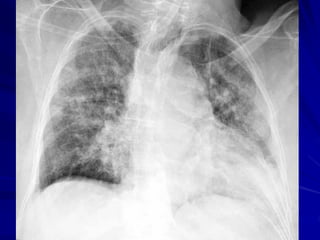

X QUANG PHỔI

Heulitt (1988): Xquang có:

Độ nhạy cảm: 45 %

Độ đặc hiệu: 92 %

X quang: dấu hiệu chỉ điểm kém cho

nguyên nhân VP

• Không có hình ảnh Xquang đặc hiệu

cho VP do virus, TN không điển hình

• Không thể giúp phân biệt VP do VT

hay do virus

• VP thùy/Xquang: giá trị cao cho VP vi

trùng nếu kèm sốt cao (39oC), BC tăng

(>20.000/mm3) (Spec=74%)

XQ NGỰC

Không khuyến cáo chỉ định thường quy ở

BN ngoại trú.

Cần được chỉ định khi:

– VP nặng cần nhập viện

– VP kém đáp ứng với điều trị ban đầu theo

kinh nghiệm

– Có biểu hiện lâm sàng không rõ ràng

– Nghi ngờ có biến chứng (tràn dịch, tràn khí

màng phổi, …)

– Cần chẩn đoán phân biệt.